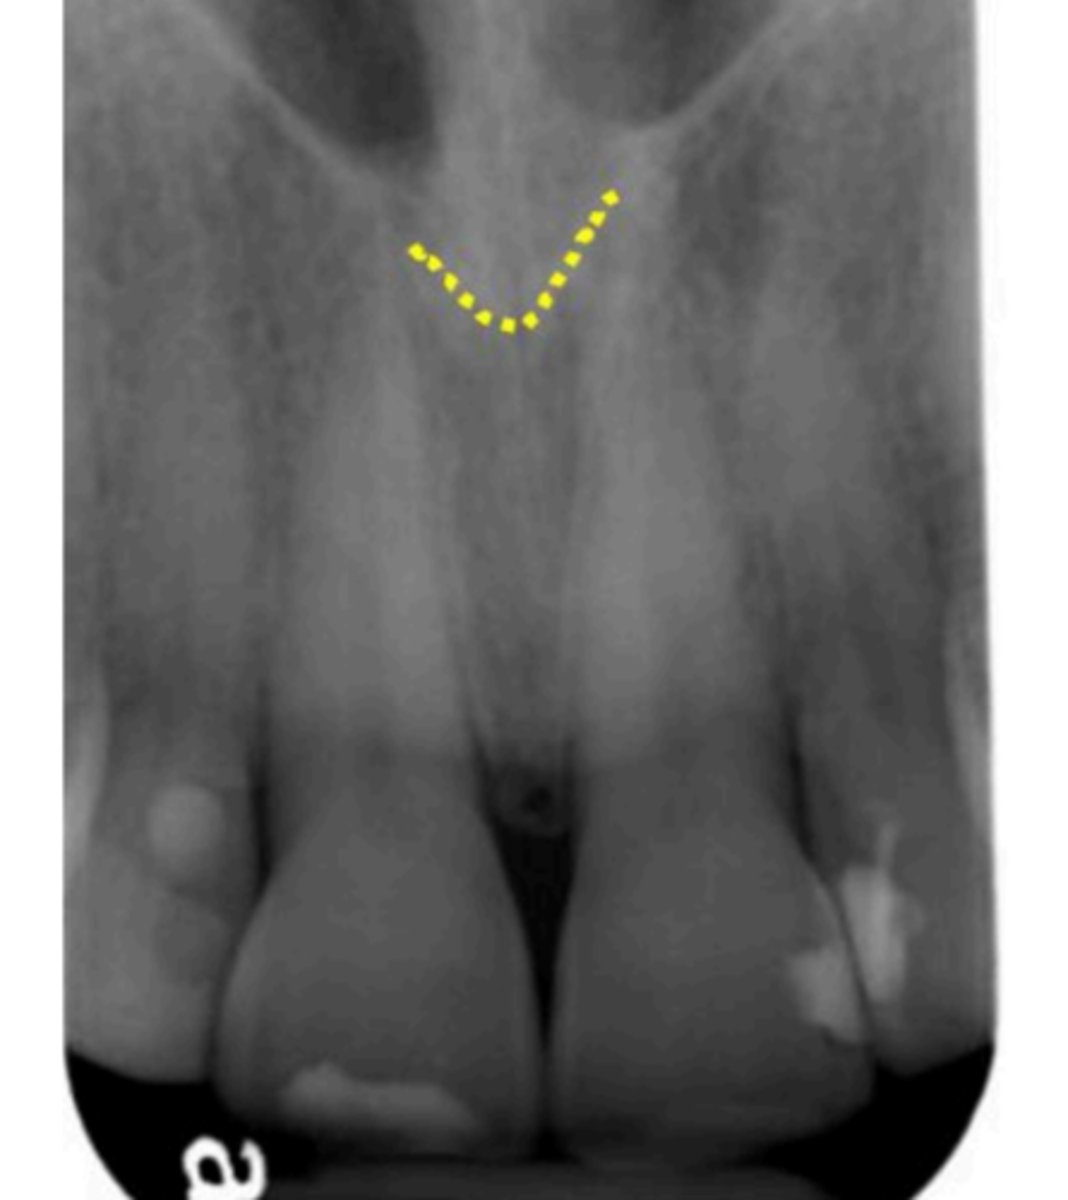

57

New cards

Mandibular canal

What is causing the thick radiolucent line surrounding the dotted line?

<p>What is causing the thick radiolucent line surrounding the dotted line?</p>

Anterior nasal spine

What is the V-shaped radiopacity indicated?

<p>What is the V-shaped radiopacity indicated?</p>

63